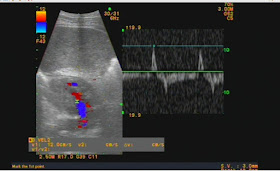

US SCANNING OF EPIGASTRIC AREA  DETECTED ONE MASS NEAR AORTA IN RETROPERITONEUM  # 4 CM   WITH DOPPLER  FLOW IN THIS MASS

US 1: PW DOPPLER SHOWS ARTERY FLOW PATTERN

US 2: THIS FLOW IS CONNECTED TO AORTA.